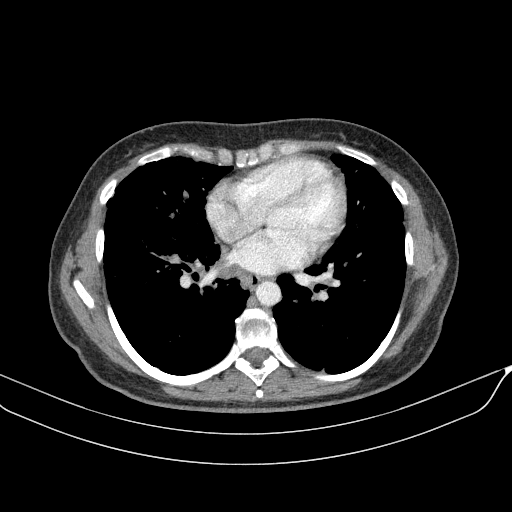

Targeted Slice 70 - Mediastinum Window Analysis (Generated vs Real Venous)

0.762

Mediastinum SSIM

47.9

Mediastinum RMSE

17.1

Mediastinum MAE

Average Mediastinum Window Metrics Across All Slices (133 slices) - Generated vs Real Venous

0.740

Mediastinum SSIM (Avg)

46.9

Mediastinum RMSE (Avg)

17.0

Mediastinum MAE (Avg)

Generated VENOUS CT scan (A→B translation)

Mediastinum window (WL 40, WW 400 β†’ Low βˆ’160, High +240)